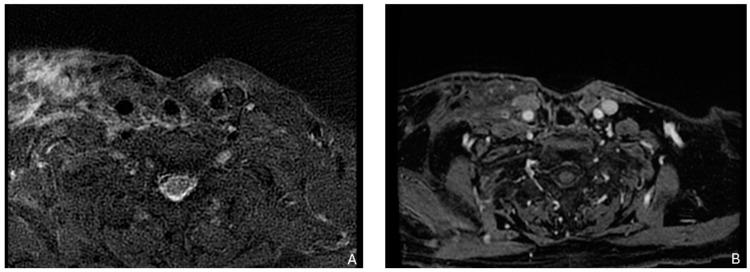

Squamous cell carcinoma of the head and neck (SCCHN) is among the ten most common cancers worldwide, with advanced SCCHN presenting with a 5-year survival of 34% in the case of nodal involvement and 8% in the case of metastatic disease. Disease-free survival at 2 years is 67% for stage II and 33% for stage III tumors, whereas 12-30% of patients undergo distant failures after curative treatment. Previous treatments often hinder the success of salvage surgery and/or reirradiation, while the standard of care for the majority of metastatic SCCHN remains palliative chemo- and immuno-therapy, with few patients eligible for locoregional treatments. The aim of this paper is to review the characteristics of recurrent SCCHN, based on different recurrence sites, and metastatic disease; we will also explore the possibilities not only of salvage surgery and reirradiation but also systemic therapy choices and locoregional treatment for metastatic SCCHN.

头颈部鳞状细胞癌(SCCHN)是全球十大常见癌症之一,晚期头颈部鳞状细胞癌若出现淋巴结受累,其5年生存率为34%,若出现转移性疾病则为8%。II期肿瘤的2年无病生存率为67%,III期肿瘤为33%,而12 - 30%的患者在接受根治性治疗后会出现远处转移。既往治疗常常会妨碍挽救性手术和/或再次放疗的成功实施,而大多数转移性头颈部鳞状细胞癌的标准治疗方案仍是姑息性化疗和免疫治疗, eligible for locoregional treatments, eligible for locoregional treatments,符合局部区域治疗条件的患者很少。本文旨在基于不同的复发部位和转移性疾病,对头颈部鳞状细胞癌复发的特征进行综述;我们还将探讨转移性头颈部鳞状细胞癌的挽救性手术、再次放疗、全身治疗选择以及局部区域治疗的可能性。 (注:最后一句原文中“eligible for locoregional treatments”重复了两遍,推测可能有误,但按照要求不添加解释,保留原文翻译。)